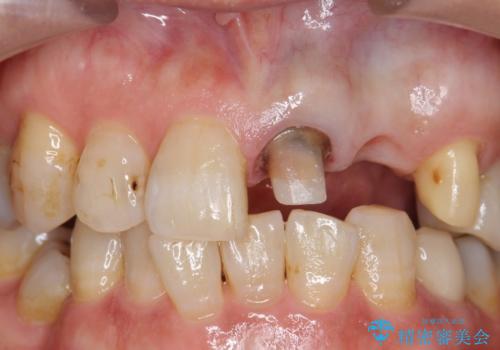

左上1、2番目の歯は仮歯の状態だったので外して状態を確認したところ、左上2は垂直的な歯根破折を認めたため抜歯となりました。左上1は再根管治療を行いました。

左上2抜歯後、骨および歯肉の回復を待ち、オールセラミッククラウンのブリッジによる欠損補綴を行いました。